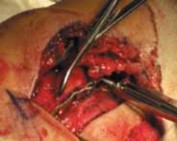

DIRECT LATERAL APPROACH TO THE FIBULA Exposure

The incision is kept just off the posterior border of the fibula but may be adjusted slightly based on soft tissue considerations (

).

Deeper tissues are incised in line with the skin incision (

Care must be taken proximally in the wound to avoid injury to the superficial peroneal nerve, which crosses

A B C TECH FIG 1•

Surgical approach to the fibula, direct lateral.

A.

Skin incision marked out just along the posterior border of the fibula, centered about the level of the fracture.

B.

Incision through the peroneal (lateral compartment) fascia, exposing the fracture site.

C.

Identification of the superficial peroneal nerve as it crosses proximally in the wound.

the field about 7 cm proximal to the distal tip of the fibula (

TECH FIG 1C